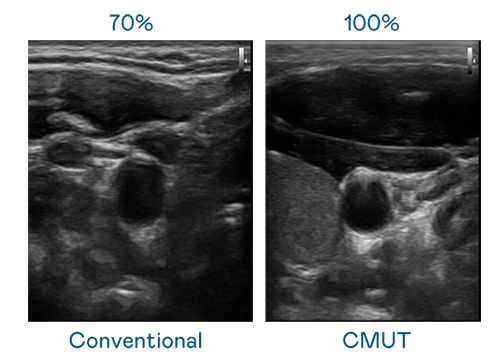

CMUT 技術是一種用電容式微機電元件來產生超音波訊號的技術。與傳統 PZT 壓電式技術相比,CMUT 頻寬增加 30%,更寬頻的超音波訊號讓影像解析度大幅提升,是實現高影像品質醫療超音波掃描、促進精準醫療發展的關鍵技術。

大頻寬帶來超清晰影像

超音波影像的解析度高低,首先取決於探頭能發出的訊號頻寬。腾龙集团 CMUT 可提供高清晰的超音波訊號,提供高頻寬、高靈敏度、影像紋理細節更高的超音波影像,協助醫護人員縮短影像判讀時間及利用精準的醫療影像進行診斷。